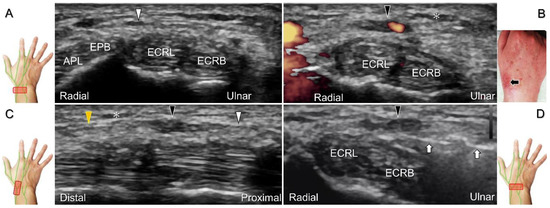

Scanning Technique

With the forearm supinated, the transducer is positioned in the axial plane at the lateral aspect of the antecubital fossa. The superficial and deep radial nerves are situated between the brachioradialis and brachialis muscles. The superficial radial nerve initially courses next to the radial artery below the brachioradialis muscle, and then departs from the radial artery in the distal third of the forearm (Figure 21A). Distally, it pierces the antebrachial fascia between the extensor carpi radialis longus and brachioradialis tendons. When tracking the terminal portion of the superficial radial nerve, the forearm can be pronated, as it courses toward the dorsal radial aspect of the wrist/hand. The superficial radial nerve travels above the proximal intersection junction between the first and second dorsal extensor compartments (Figure 21B). Later, it divides into the dorsomedial and dorsolateral branches. The former courses above the distal intersection junction of the second and third compartments (Figure 21C). The latter runs beside the extensor pollicis longus tendon (Figure 21D).

Clinical Implication

Cheiralgia paresthetica, also known as Wartenberg’s syndrome, is the compressive neuropathy of the superficial radial nerve. Symptoms such as tenderness, numbness, and allodynia can be exacerbated by wrist flexion and ulnar deviation. The nerve can be compressed by a handcuff, watch, bracelet, metal implant, ganglion cyst, or distal radius fracture. Nerve entrapment commonly takes place at the proximal intersection zone pertaining to the first and second extensor compartments (Figure 22).

Additionally, acupuncture and cannulation of the cephalic vein over the distal forearm can lead to nerve injury. To prevent iatrogenic injury, the superficial radial nerve before injection should also be recognized for de Quervain’s syndrome (Figure 23A) [44], ganglion cyst aspiration (Figure 23B), and catheterization (Figure 24A–C). For injection of the superficial radial nerve, an in-plane approach in the nerve’s short axis is preferred (Figure 24D).

For those receiving surgery such as fixation or debridement of the radial wrist, the nerve can be occasionally injured, resulting in residual numbness, allodynia, dysesthesia, or hypoesthesia (Figure 25).

Figure 25. Sonographic images depict the location of a neuroma of the superficial radial nerve. The normal/proximal segment (A) and the neuroma in short-axis (B) and long-axis (C) views are seen. White arrowhead: superficial radial nerve; black arrowheads: neuroma; APL: abductor pollicis longus tendon; EPB: extensor pollicis brevis tendon; ECRL: extensor carpi radialis longus tendon; C: cephalic vein.

Figure 21. Sonographic imaging (short-axis view) of the superficial radial nerve from the distal third of the supinated forearm (A). With the pronated forearm, the nerve is seen to travel above the proximal intersection junction (B), divide into the dorsomedial branch coursing above the distal intersection junction (C), and the dorsolateral branch running beside the extensor pollicis longus tendon (D). Arrowheads: superficial radial nerve; white arrow: dorsomedial branch; black arrow: dorsolateral branch. RA: radial artery; APL: abductor pollicis longus tendon; EPB: extensor pollicis brevis tendon; ECRL: extensor carpi radialis longus tendon; ECRB: extensor carpi radialis brevis tendon; EPL: extensor pollicis longus tendon; C: cephalic vein.

Diagnostics 13 01928 g021

Figure 22. Sonographic imaging (short-axis view) of the dorsolateral branch of the superficial radial nerve at normal (A), swollen (B), and compressed (C) segments. White arrowhead: normal segment; black arrowhead: swollen segment; orange arrowhead: entrapped segment. ECRL: extensor carpi radialis longus tendon; ECRB: extensor carpi radialis brevis tendon; EPL: extensor pollicis longus tendon.

Diagnostics 13 01928 g022

Figure 23. Sonographic imaging of the superficial radial nerve beside the first extensor compartment of the wrist (A), and a ganglion cyst over the second extensor compartment of the wrist (B). White arrowheads: superficial radial nerve; white arrow: needle. APL: abductor pollicis longus tendon; EPB: extensor pollicis brevis tendon; ECRL: extensor carpi radialis longus tendon; ECRB: extensor carpi radialis brevis tendon.

Diagnostics 13 01928 g023

Figure 24. Sonographic imaging of the superficial radial nerve entrapment due to a post-surgical scar. Short-axis imaging at the normal (A) and the swollen (B) segment proximal to the entrapment. The normal, swollen, and entrapped segments of the nerve are seen in long-axis view (C). Ultrasound-guided hydrodissection of the nerve from the ulnar aspect (D). White arrowheads: normal segment; black arrowheads: swollen segment; orange arrowhead: entrapped segment; white arrows: needle; black arrow: scars on the skin; asterisk: scars in the subcutaneous tissue; APL: abductor pollicis longus tendon; EPB: extensor pollicis brevis tendon; ECRL: extensor carpi radialis longus tendon; ECRB: extensor carpi radialis brevis tendon.

Diagnostics 13 01928 g024